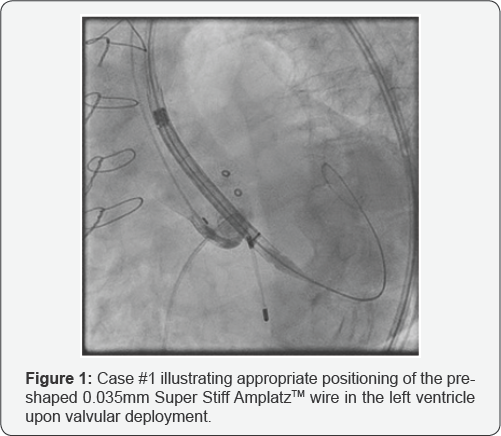

Transfemoral placement of a 26mm CER valve was performed across the previous prosthesis using a pre-shaped 0.035mm Super Stiff Amplatz™ (Boston Scientific, Oakland, NJ) wire with a 1cm soft-tip as a rail (Figure 1). The TAV was deployed while pacing at 120 beats/min with an initial implant depth of 10mm and significant paravalvular leak. The CER was subsequently recaptured fully and redeployed at a depth of 7mm with resolution of leak. At this point, the patient suffered cardiac arrest. Emergent sternal re-entry revealed an LV tear from the wire lateral to the left anterior descending artery. The patient expired after several failed attempts at repairing the myocardium.